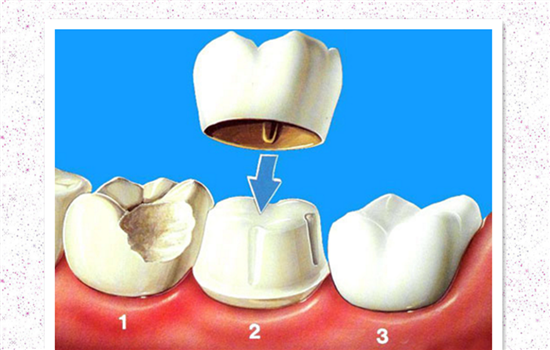

利用全瓷冠进行修复

假如牙齿裂纹较大,连牙根也裂了,可以进行全瓷冠修复治疗,通常通过这种方法修复治疗后,牙齿可以用十年以上的时间。

利用牙套进行修复

现在有很多人牙齿出现裂纹的原因是蛀牙、死髓牙等疾病,最好是利用牙套来进行修复治疗,金属冠修复也是可行的,修复后牙齿可以恢复正常的咀嚼功能,而且这种修复方法也比较经济实惠。